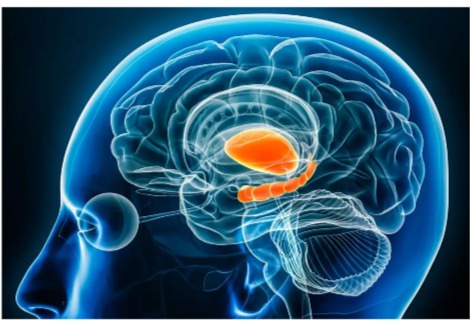

افترضت النظريات السابقة أن التعب الذي يعاني منه الناس من المجهود العقلي ينبع من استنفاد احتياطيات الطاقة. كتب مؤلفو الدراسة أن البحث لم يؤكد ذلك. بدلاً من ذلك ، افترض ويهلر وزملاؤه أن شيئًا ما كان يتراكم في الدماغ ، لذلك بحثوا عن دليل على ذلك في منطقة تساعد في تنظيم التحكم المعرفي: قشرة الفص الجبهي الأيسر.

توضح التطبيقات أنه بالإضافة إلى مساعدتنا في القيام بمهام معقدة مثل حل أحجية سودوكو أو لعب الشطرنج أو تصميم تجربة ، فإن القشرة الجانبية اليسرى تساعد في التحكم في العمليات المطلوبة لتذكر المعلومات ومعالجتها لحل تلك المشكلات. "إنه أيضًا جزء من النظام الذي يقول ،" حسنًا ، في الواقع ، ربما لا أريد أن ألعب الشطرنج. أرغب في مشاهدة فيلم والقيام بشيء أكثر بساطة ".